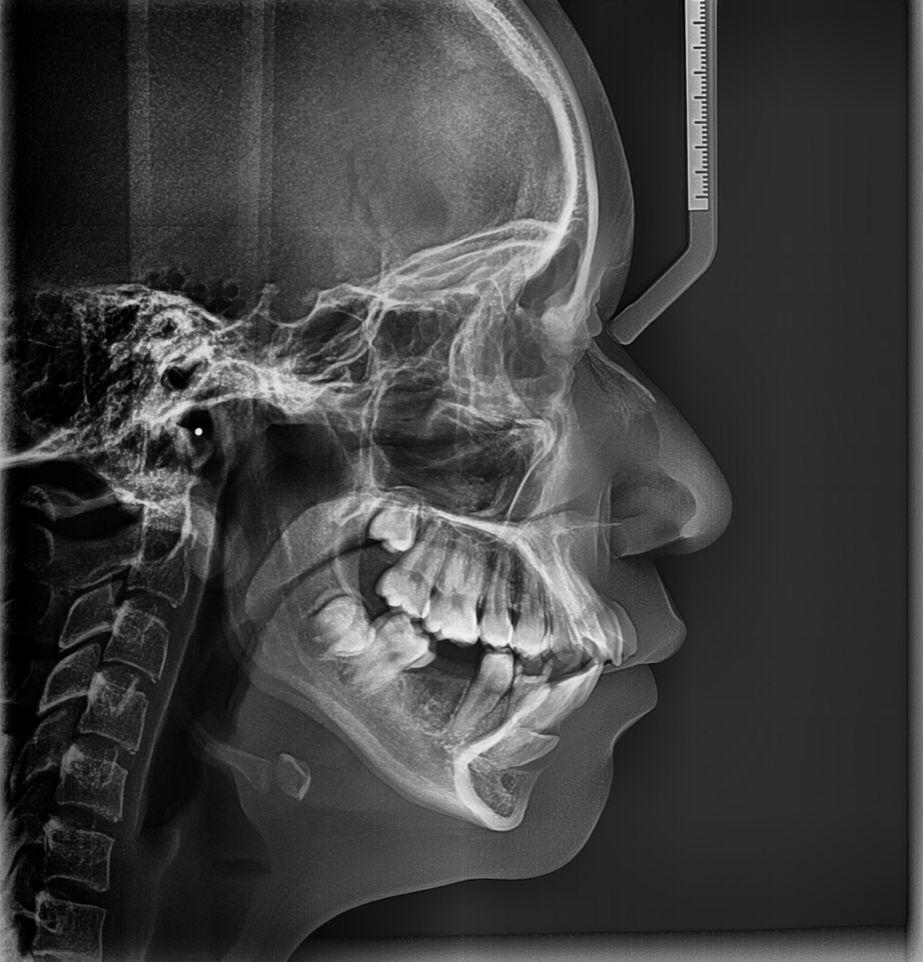

- Radiografía lateral de cráneo

- Cefalometría computarizada